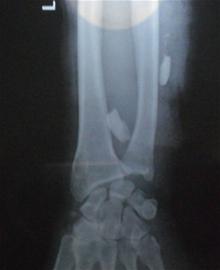

記者趕到401醫院時,醫生正在為受傷老人做檢查。記者發現老人左前臂纏上了厚厚的紗布,而且手腕處的傷口鮮血還不斷往外滲,醫生用繃帶將傷臂吊在脖子上。老人的右胳膊也有傷口,手腕處纏了厚厚的繃帶。此外,老人的雙手多處劃傷,滿是暗紅色的血漬。醫生在檢查的過程中,老人家屬向醫生出示了在當地醫院拍攝的X光片,通過X光片可以清晰地看到插入胳膊中的兩顆豬牙。醫護人員診斷后將老人送到手術室準備手術。

中午12時左右,醫生為劉老漢取出了胳膊中的兩顆豬牙,在將傷口消毒后,沒有縫合而是仔細包扎起來。“我們擔心豬牙中有毒性,所以對傷口進行消毒處理后沒有立即縫合。在這個過程中,毒素可能通過膿液從傷口中排出,等傷口處長出新肉,確認沒有感染后,醫生會選擇適合的時間再進行縫合手術。”負責該手術的醫護人員向記者介紹說。